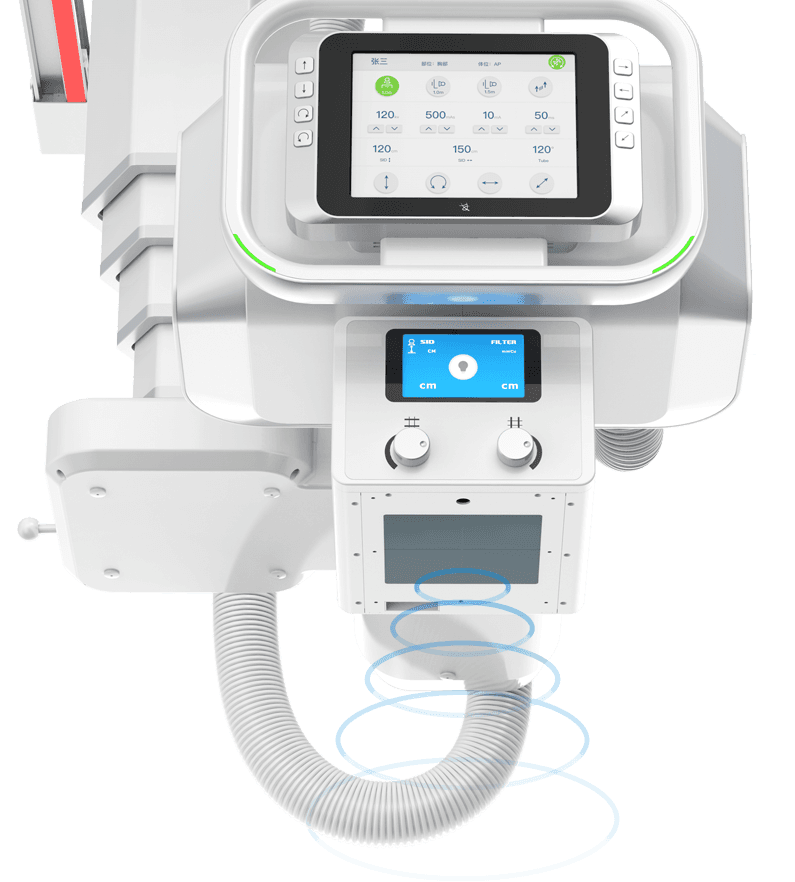

ОЮПЯТЈїШІЩЧч

Ед±ёОЮПЯТЈїШЖчЈ¬ТЈїШБйГфЈ¬Йи±ёФЛ¶Ї·ґУ¦СёЅЭЈ¬

И«іМЦ§іЦёфКТТЈїШІЩЧчЎЈ -

»ъјЬДЪЦГУпТф¶ФЅІПµНі

»ъЙнДЪЦГЧЁТµТЅУГ¶ФЅІПµНіЈ¬УпТфПµНіІЙУГёЯ±ЈХжТфР§ЙијЖЈ¬ТфЦКЗеОъєйББЎЈ

ІЩЧчТЅК¦їЙёфКТЅшРРУпТфЦёµј°ЪО»ЙгЖ¬Ј¬»јХЯФЪ»ъ·їДЪїЙЗеОъЅУКЬКТНвІЩЧчТЅК¦УпТфЦёБоЈ¬МбЙэ°ЪО»ЙгЖ¬јмІйµД°ІИ«РФУлР§ВКЎЈ